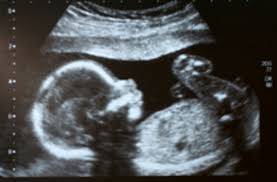

This is because tests to diagnose cancer and treatments can affect the fetus, so each step in your medical care will be done carefully. Studies have shown that a woman's risk of developing breast cancer is related to her exposure to hormones that are produced by her ovaries (endogenous estrogen and progesterone).reproductive factors that increase the duration and/or levels of exposure to ovarian hormones, which stimulate cell growth, have been associated with an increase in breast cancer risk. Sometimes we can tell because the baby's liver is enlarged. What is cancer of the uterus? Endometrial cancer, the most common form, begins in the inner lining of the uterus.

Fetal Multicystic Dysplastic Kidney Mcdk What You Need To Know from www.massgeneral.org Scientists have established beyond doubt that cancer can be transmitted from mother to baby in the womb, but australian women have been told the incidence is ''extraordinarily rare'' and no cause for alarm. The endometrium is the lining of the womb. Womb cancer is the fourth most common cancer in women in the uk but very few women recognise the symptoms, according to a cancer. Still, some women may be told to wait a number of years before trying to have a baby. Many people don't realize how strong a baby in the womb can be. The cancer can develop from abnormal cells in the lining of the uterus (endometrium) or the muscle tissue. There has however been no clear genetic evidence to support this interpretation, which was shown unambiguously by our study for the first time, mizutani said. Often, pregnancy after cancer treatment is safe for both the mother and baby.

When it does happen, cancer during pregnancy can be more complex to diagnose and treat. It may cause pain, swelling (a lump), or both. And smoking while you're pregnant can cause serious problems, too. This is especially in women who have stopped having periods (post menopausal women). Most women with womb cancer will have a type called endometrial cancer. They are called endometrial cancers. Scientists have established beyond doubt that in rare cases cancer can be transmitted in the womb, following the birth of a baby to a woman with leukaemia. Many people don't realize how strong a baby in the womb can be. Vaginal bleeding after the menopause. Sometimes we can tell because the baby's liver is enlarged. It can increase womb cancer risk, as it is thought to have a similar effect to oestrogen on the womb. Womb cancer happens when cells in your womb (uterus) grow in an abnormal and uncontrolled way, forming a lump or tumour. This is because tests to diagnose cancer and treatments can affect the fetus, so each step in your medical care will be done carefully.

The discovery was made by scientists in britain when a baby developed cancer a few months after her mother died from leukaemia. It makes up about 3% of childhood cancers. The suspicion has been that the cancer may have developed in the pregnant woman but then spread to the baby in the womb. Most women with womb cancer will have a type called endometrial cancer. However, chemotherapy drugs and certain radioactive components can get into breast milk and harm the baby.